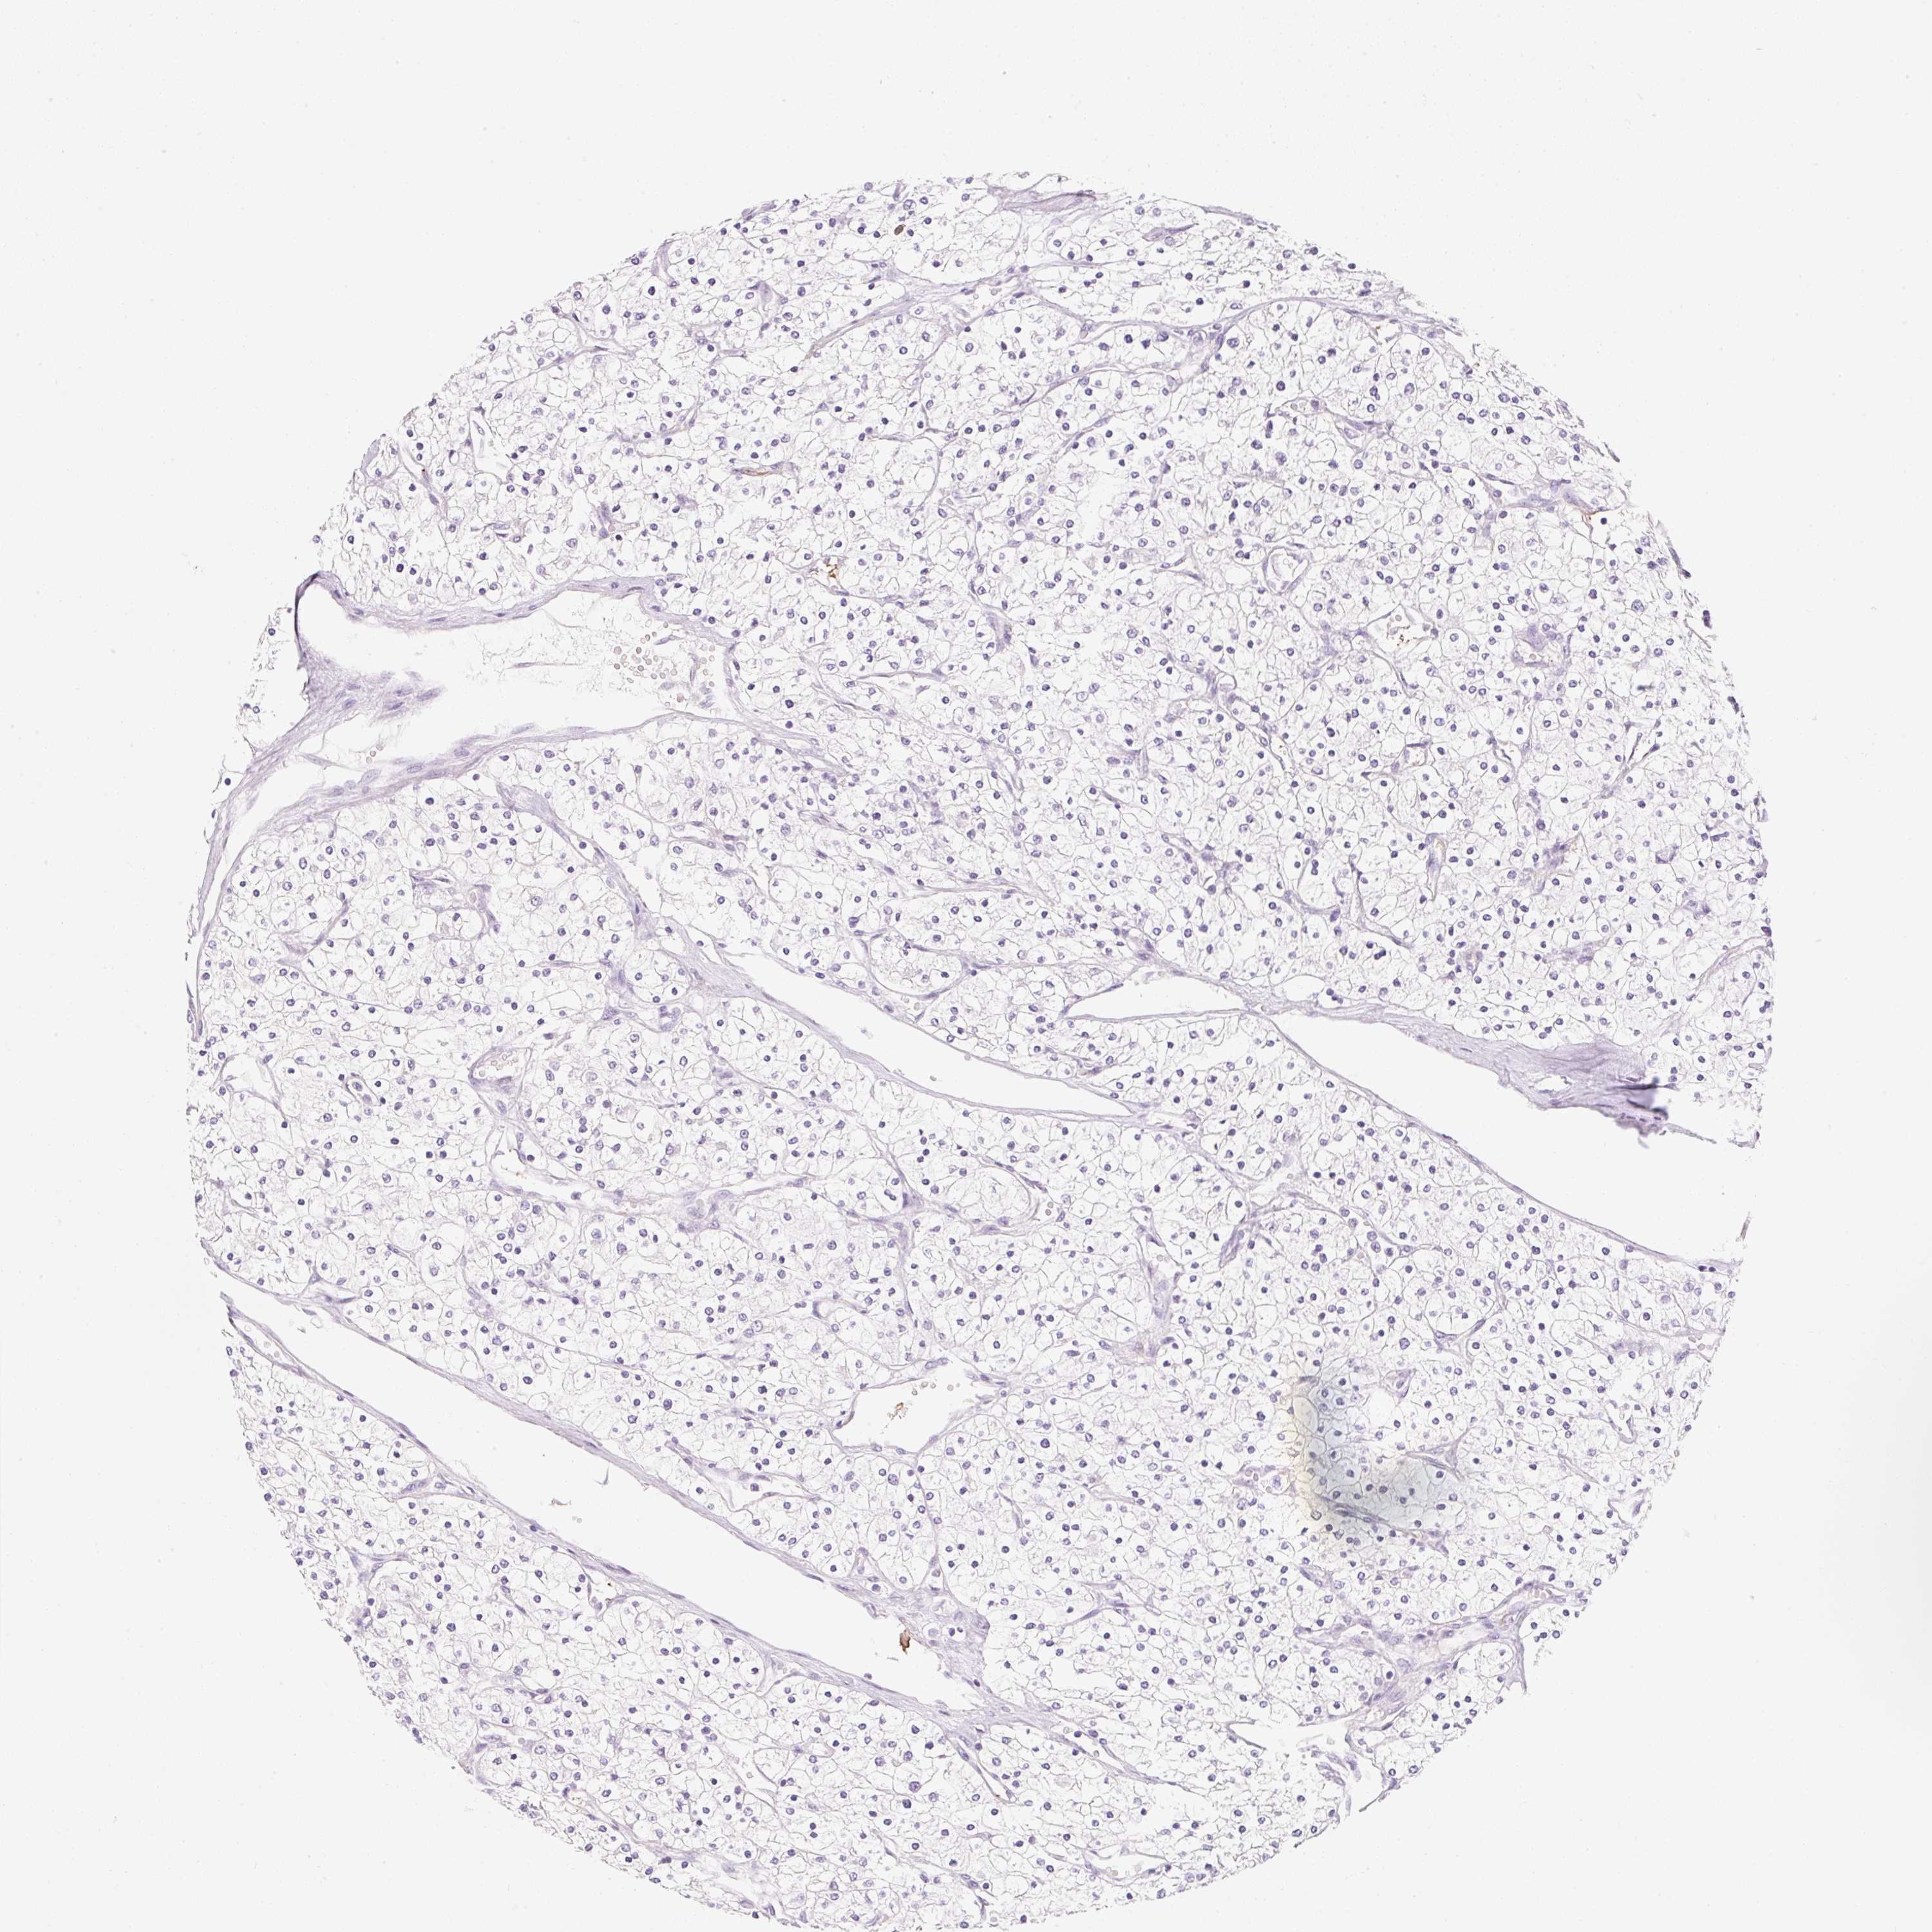

Renal cancer

Kidney renal papillary cell carcinoma

KIDNEY RENAL PAPILLARY CELL CARCINOMA (TCGA) - Interactive survival scatter ploti

The Survival Scatter plot shows the clinical status (i.e. dead or alive) for all individuals in the patient cohort, based on the same data that underlies the corresponding Kaplan-Meier plots. Patients that are alive at last time for follow-up are shown in blue and patients who have died during the study are shown in red.

The x-axis shows the expression levels (FPKM) of the investigated gene in the tumor tissue at the time of diagnosis. The y-axis shows the follow-up time after diagnosis (years). Both axes are complimented with kernel density curves demonstrating the data density over the axes. The top density plot shows the expression levels (FPKM) distribution among dead (red) and alive patients (blue). The right density plot shows the data density of the survived years of dead patients with high and low expression levels respectively, stratified using the cutoff indicated by the vertical dashed line through the Survival Scatter plot. This cutoff is automatically defined based on the FPKM cutoff that minimizes the p-score. The cutoff can be changed by dragging the vertical line or by entering a cutoff value in the square labeled "Current cut-off".

Under the Survival Scatter plot the p-score landscape (black curve; left axis) is shown together with dead median separation (red curve; right axis). Dead median separation is the difference in median mRNA expression between patients who have died with high and low expression, respectively. It is calculated as follows: median FPKM expression of dead patients with high expression - median FPKM expression of dead patients with low expression. This is intended to aid the user in visually exploring custom cutoffs and the associated p-scores and dead median separation.

Individual patient data is displayed and can be filtered by clicking on one or more of the category buttons on the top of the page. Categories describing expression level and patient information include: high, low, alive, dead, female, male and tumor stages. The scale of the x-axis can be toggled between linear and log-scale by clicking on the "x log" button. Mouse-over function shows TCGA ID, patient information and mRNA expression (FPKM) for each patient.

& Survival analysisi

Kaplan-Meier plots summarize results from analysis of correlation between mRNA expression level and patient survival. Patients were divided based on level of expression into one of the two groups "low" (under cut off) or "high" (over cut off). X-axis shows time for survival (years) and y-axis shows the probability of survival, where 1.0 corresponds to 100 percent.

FABP5 is not prognostic in Kidney Renal Papillary Cell Carcinoma (TCGA)